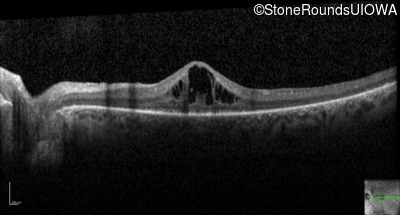

Optical Coherence Tomography - Right - 20/25

Exemplar / OCT Stack